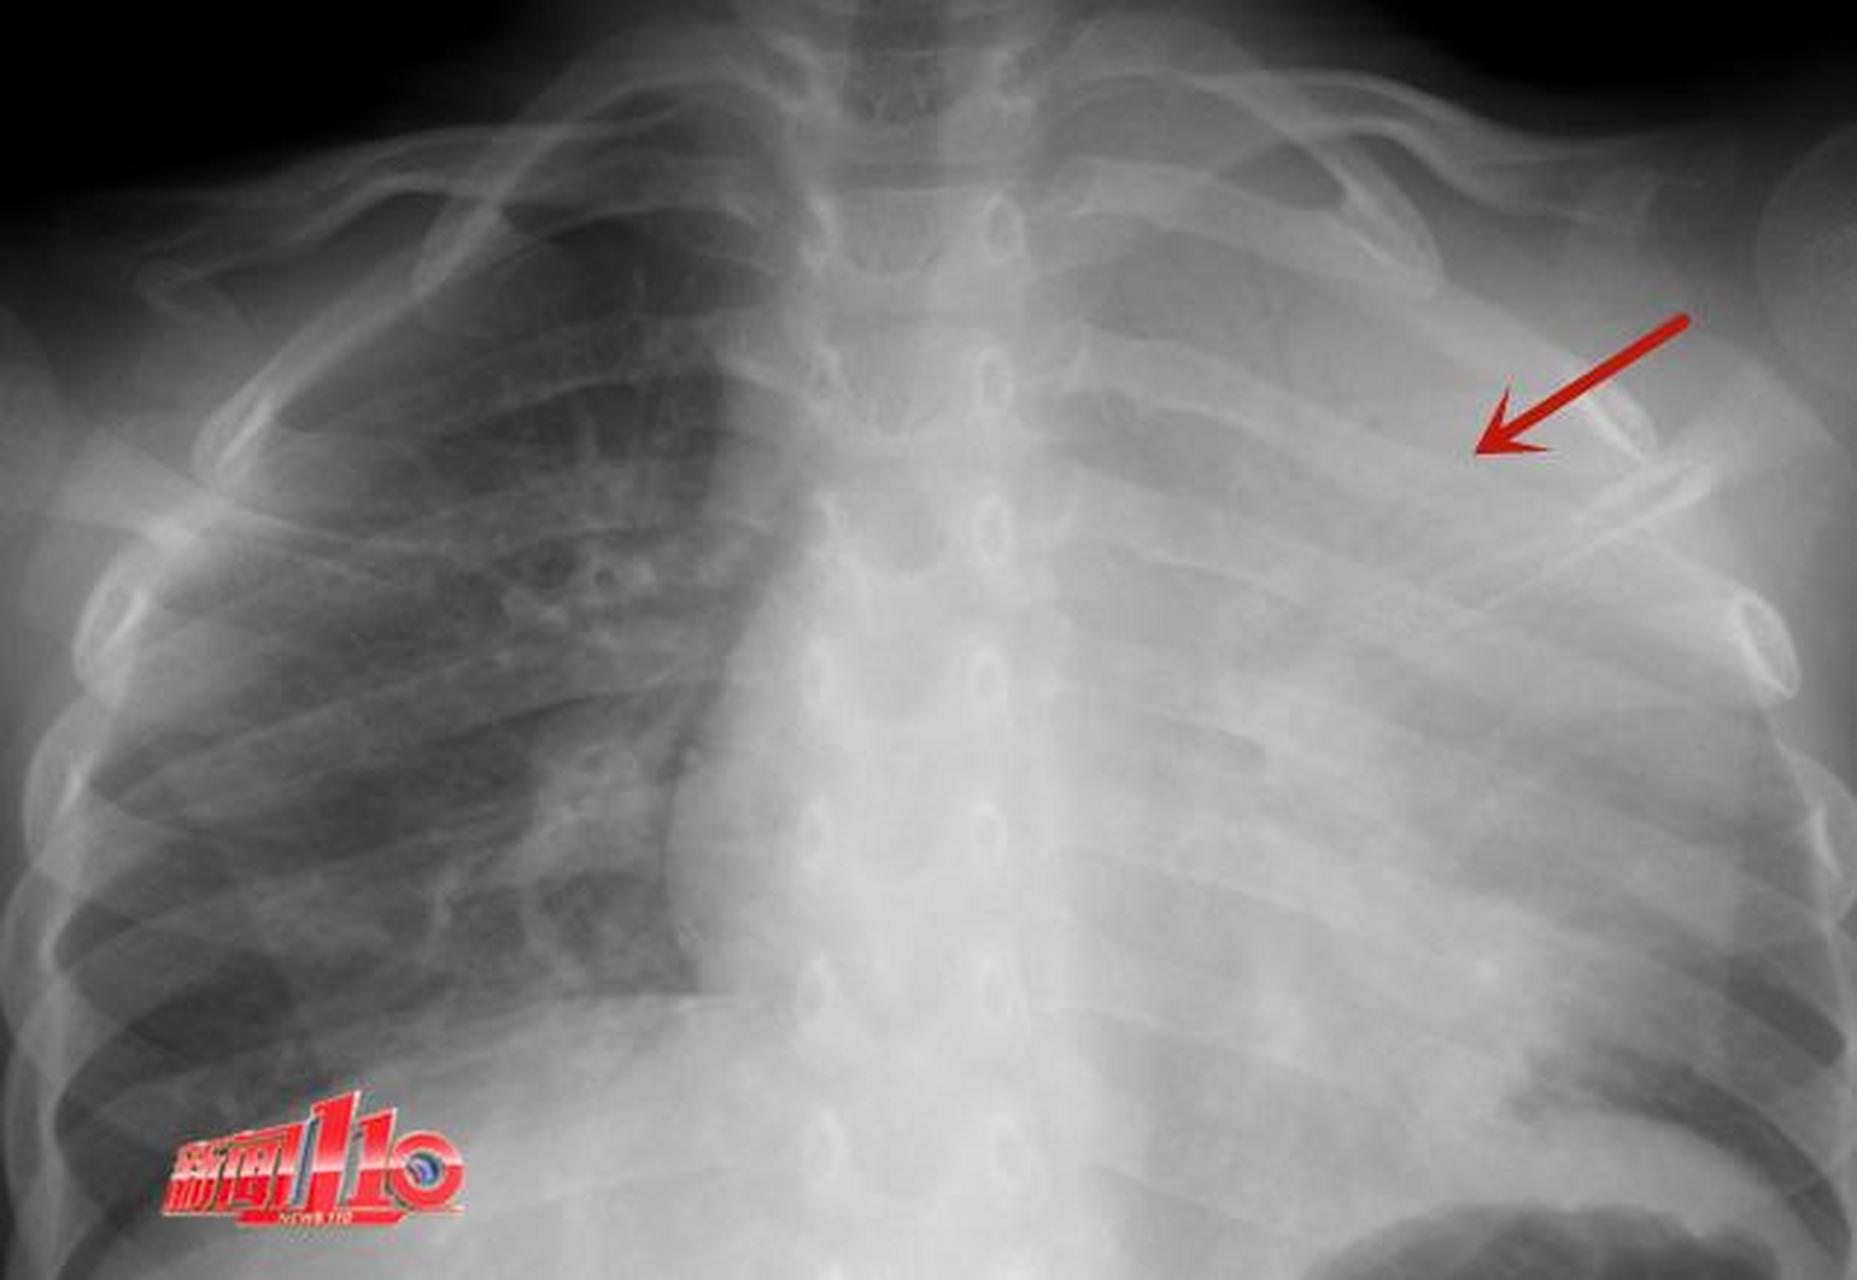

【福州6岁女童反复发烧,左肺接近白肺!这种疾病目前处于发病小高峰!】

图片尺寸1857x1280